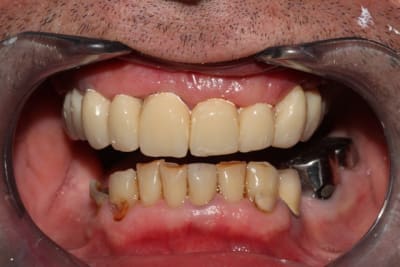

Suite du boulot: le bas

Quelques semaines plus tard, on prépare 37 36 34, ainsi que la 44, conservée vivante. J'ai hésité à aller chercher un ancrage radiculaire, étant donné le peu de hauteur de la couronne clinique, en fin de compte la CCM sera collée au superbond. Là encore, surfaçage/curetage rotatif des poches le jour de la préparation (sur 36 et 37 exclusivement)

Provisoires.

Séances suivantes (2 séances je crois), reprise des traitements endo, réalisation des RCR/tenons fibrés. Empreinte.

Réalisation des CCM+bridge selon courbe d'occlusion idéalisée, je retoucherai le provisoire maxillaire le jour de la pose.

Pose du bas, nous sommes en décembre, à la mandibule tout est propre, on va pouvoir s'occuper plus sérieusement du maxillaire à la rentrée.

(photos avec pro en place réalisées au fauteuil)